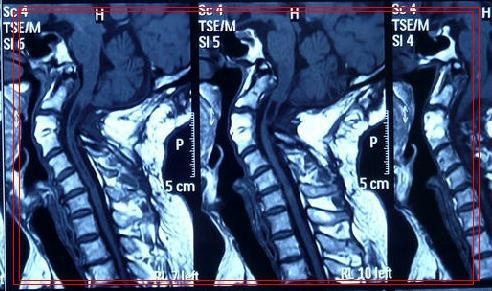

治疗:手术——后路减压术

术后影像学